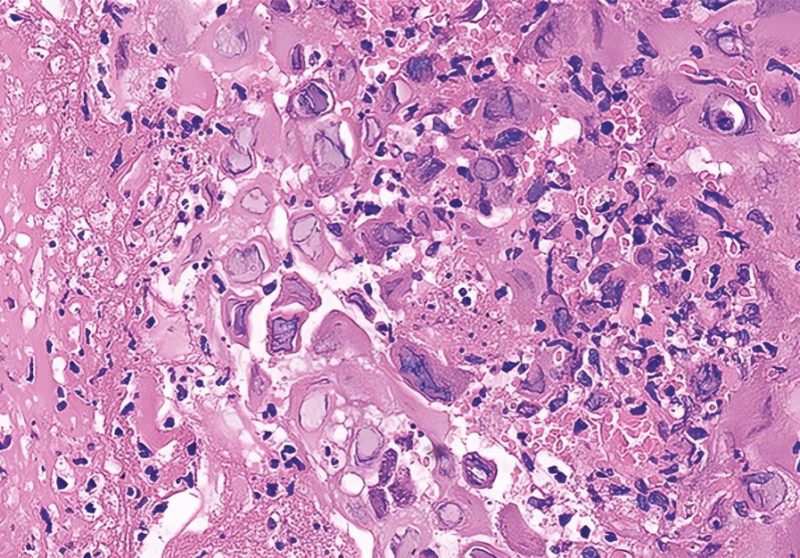

”56, female, presents with difficulty swallowing 140 days after allogeneic transplant for AML

GI scopes her, sees.

Path sees.

What’s going on?

Management?”